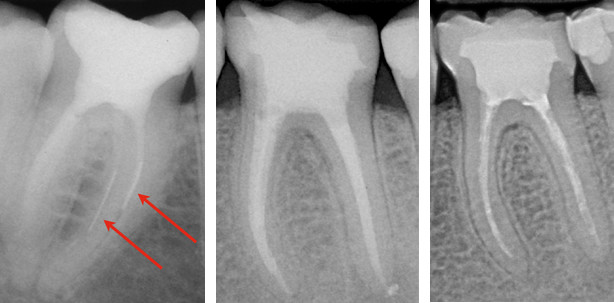

Revision

Neuere Untersuchungen propagieren, dass mit reziproken Instrumenten auch die Revision von Wurzelkanalfüllungen möglich ist. Dr. Klaus Neuhaus von der Universität Bern präsentierte erste vielversprechende Resultate zur Revision trägerbasierter Wurzelfüllmaterialien. Reziproke Instrumente können eine Alternative zu rotierenden Revisionsfeilen darstellen. Allerdings fehlt heute noch die wissenschaftliche Evidenz, welche auf eine Überlegenheit der reziproken im Vergleich zur rotierenden Bewegung für eine Wurzelkanalrevision hinweisen würde.